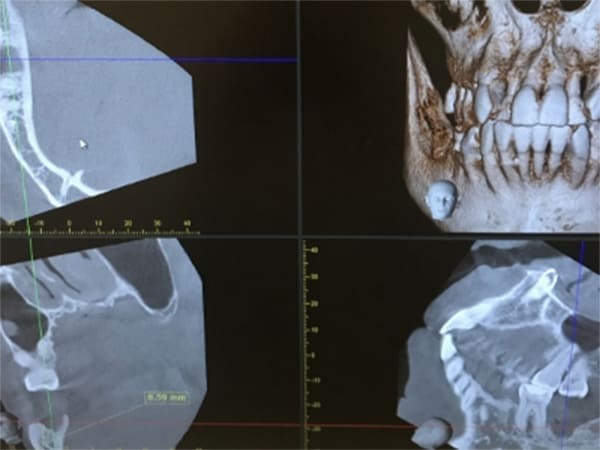

歯科用CTで隠れた部分を細部まで把握

歯科用CTはインプラントのツールとしての導入と思われがちですが、実際には「予測の診療から確実性のある診療」へ変えることができます。

従来のレントゲン撮影と違いCT撮影は、神経や血管の位置、骨の状態、病状の進行具合など、立体的な3次元の情報が視覚的に確認できます。

下顎の骨の中には重要な神経と血管が通っています。そこにインプラントのドリルが触れるなどの事態が起きれば神経が損傷して唇周囲が麻痺するなど重大な事故になります。そのため、手術前にCT撮影を行い、神経までの正確な距離を測定し、十分な安全域を見極めてから治療する必要があります。